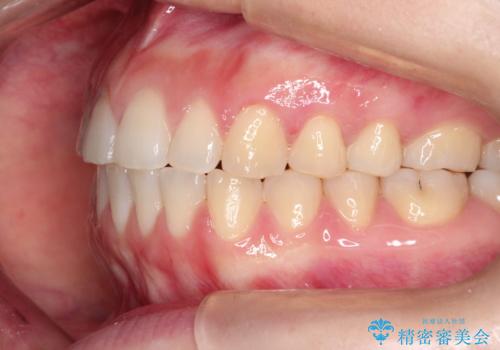

上下の前歯が当たらない インビザラインによる開咬の矯正治療

- 上下の前歯の間に隙間があるとのことで来院されました。

開咬とよばれる、奥歯しか上下の歯が接触していない状態でした。

インビザラインにて矯正治療を行うこととなりました。

使用時間を守っていただけたので、比較的スムーズに矯正を終了することができました。

前歯で物が咬み切れるようになり、喜んでいただけました。

舌の使い方が上手ではなかったので、治療と同時に舌のトレーニングを行いました。

舌の使い方も矯正治療と非常に関係があります。